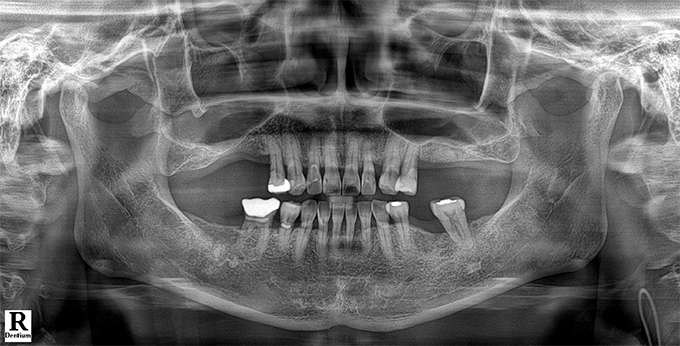

Before & After

임플란트 전후사진

before

2022.10.27

After

2022.11.21

※ 상기 치료전후 사진은 환자의 동의 하에 게재되는 것이며 동일한 촬영각도로 촬영 하였고 치료 기간을 명시하였습니다.

이러한 치료의 결과는 이 환자분에게만 해당되는 것이며 환자의 상태에 따라 똑같은 결과를 얻지 못할 수도 있습니다.

환자분의 상태에 따라 치료 기간, 효과 및 부작용은 상이할 수 있습니다.

치료전후 사진 게재는 의료법 제 23조, 제56조에 의거하여 게재합니다.